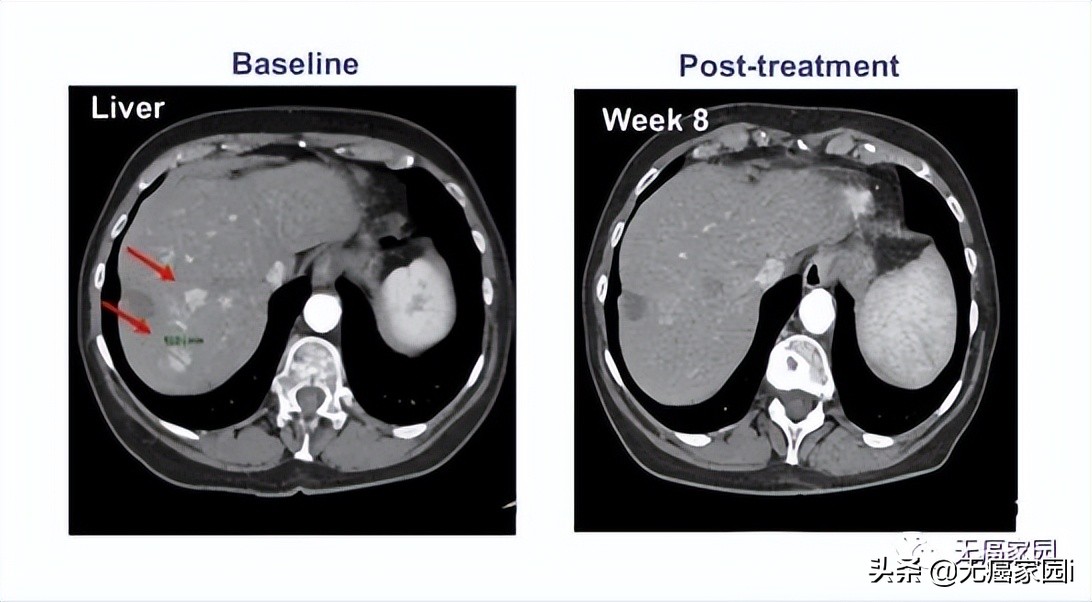

其中 1例晚期肝癌患者接受了瘤内注射CAR-T治疗,治疗后肝脏病灶代谢基本消失。

CAR-T细胞 注射60天后 ,虽然2个肺部结节的尺寸没有显著的改变,但在 第10天时肝脏肿瘤病变(1.2×1.3cm)显著收缩 , 注射GPC3-7×19 CAR-T细胞第32天后则完全消失。

患者没有任何毒性作用,并且根据 CT 上的标准实体瘤反应评估标准 (RECIST) 1.1 版进行了分期评估,显示部分缓解 (PR)。